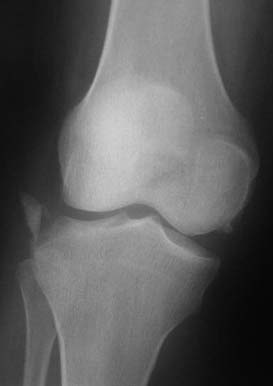

“Перелом наружного мыщелка правого бедра во фрональной плоскости был не замечен”

Диагностическая ошибка происходит, когда игнорируется правила обследования внутрисуставных переломов. Вместо полного обследования, включая КТ, ограничиваются рентгенограммой, и то в одной проекции!

Спасибо большое за советы! Добавляю некоторые КТ снимки. Перелом коллеги не диагностировали, видимо, расценив костную травму как повреждение задне-латерального комплекса коленного сустава. Отпишусь по результату выполненной операции.